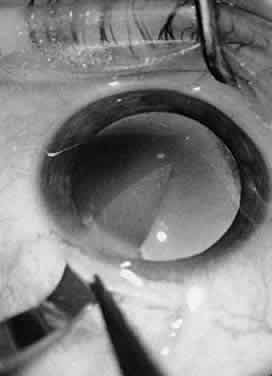

CAPSULOTOMY

Continuous curvilinear capsulorrhexis (CCC) is the method of capsulotomy creation for phaco. A 5- to 6-mm diameter CCC is beneficial because the larger the CCC, the easier the access to cortex, which thus reduces occurrence of a broken capsule; a smaller CCC often results in anterior capsule contraction with possible IOL decentration, and poor retinal visualization; a larger CCC results in decreased migration of epithelial cells that have been implicated in posterior capsule opacification.9

Performing capsulorrhexis in patients with dense, opaque cataracts can be difficult because a poor red reflex is often found. Dying the anterior capsule with indocyanine green facilitates visualization of the anterior capsule during CCC. Others have used different dyes, including trypan blue and methylene blue. However, the safety and efficacy of these products have not been thoroughly studied. Current recommendations for the indocyanine green CCC technique are as follows: